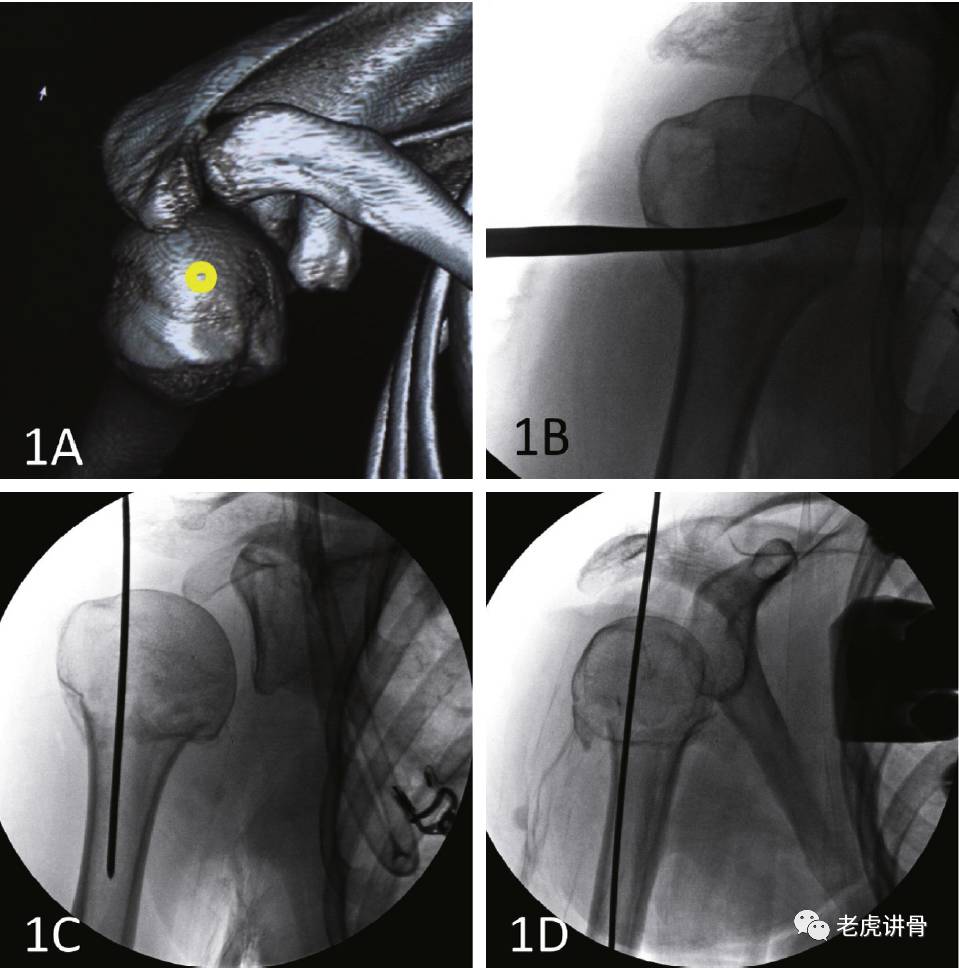

图1 沙滩椅位

图2 采用更偏内侧的入钉钉置入直的髓内钉会对肱骨头外表面造成一些损伤,但是受影响的是冈上肌而不是冈上肌肌腱(A)。置入经皮复位工具来将内翻的肱骨头向上撬起(B)。在进行髓内钉扩髓钻孔之前必需进行前后位和侧位的透视来确定正确的入钉点位置(C和D)